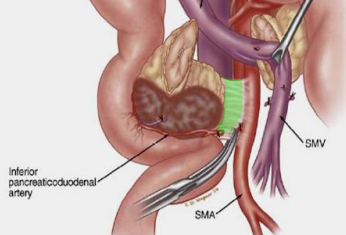

- Infiltration artérielle: <180° vs >180° et cranio-caudalement >2cm vs <2cm

- Infiltration veineuse: Contact, engainement, sténose, occlusion

- Infiltration de la lame rétroporte (entre l’AMS et l’uncus)

Lame rétroporte

Anatomie